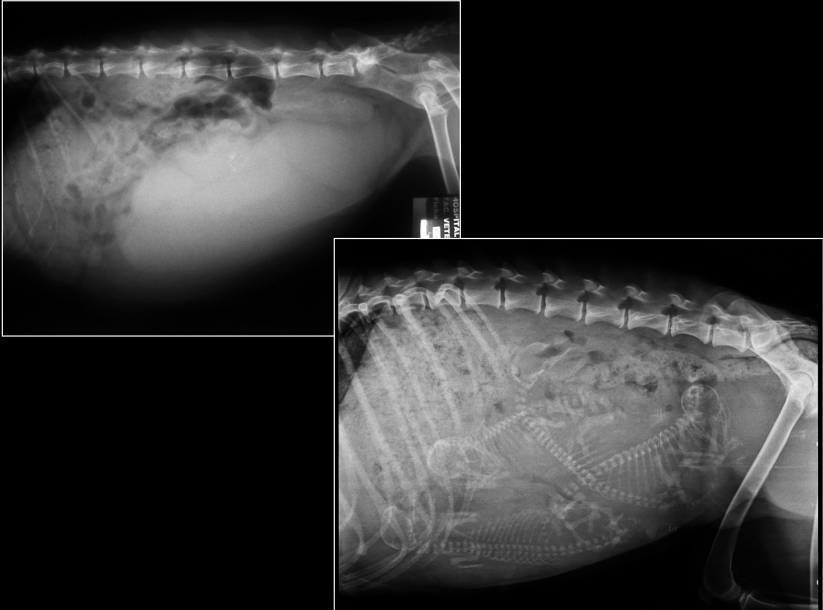

ÚTERO

- Visible cuando distendido: estructuras tubulares tortuosas en abdomen caudoventral.

- Causas:

- Fisiológico: gestación temprana

- Patológico: piómetra, hidrómetra, mucómetra, neoplasia, absceso de muñón

- Gestación: mineralización fetal visible 40–45 días.

- Muerte fetal (Si encontramos gas con los fetos), momificación, distocia (Problemas para el parto).